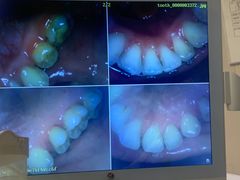

• 好大夫口腔(广州店)

• -好大夫口腔(广州店)

匿名用户 | 23-11-16

报错